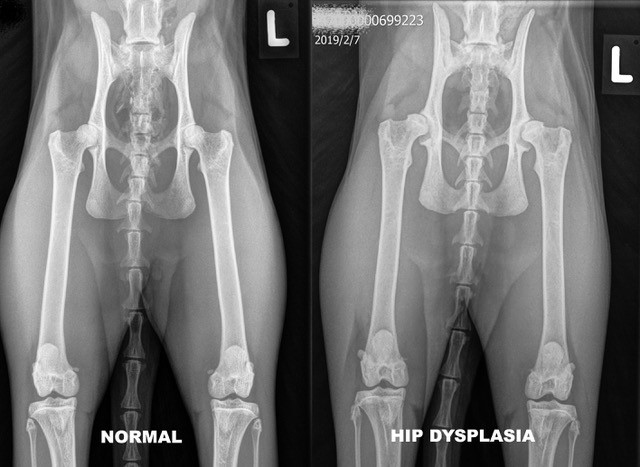

Miljontals katter i världen lider troligen av höftledsdysplasi, men katters höftledshälsa är inte särskilt väl undersökt. En färsk studie från SLU, med fokus på rasen maine coon, konstaterar att höftledsdysplasi är ärftligt och vanligare hos större katter.

Höftledsdysplasi är en välkänd och välstuderad utvecklingsrubbning hos hundar, men i dag redovisas den hittills största studie som bygger på data från katter. Det är också den första som undersöker ärftligheten för höftledsdysplasi hos katt, ett tillstånd som kan medföra lidande. Artikeln publiceras i tidskriften Scientific Reports.

– När vi analyserade data såg vi ett samband mellan stora katter och höftledsdysplasi. Vi valde då att närmare studera kopplingen mellan gener för storlek på katten och förekomsten av höftledsdysplasi. Vi konstaterade att när rasens katter ökar i storlek så blir höfterna också sämre. Därför är det ingen bra idé att selektera för ytterligare ökad storlek i aveln, säger Matt Low, forskare vid SLU:s institution för ekologi.